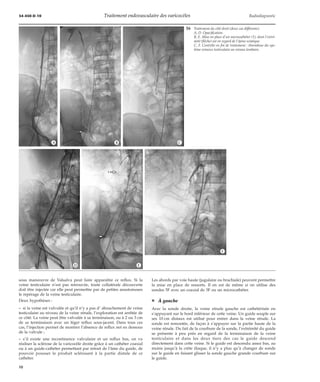

Les abords par voie haute (jugulaire ou brachiale) peuvent permettre

¦ À gauche

Avec la sonde droite, la veine rénale gauche est cathétérisée en

s’appuyant sur le bord inférieur de cette veine. Un guide souple sur

ses 10 cm distaux est utilisé pour entrer dans la veine rénale. La

sonde est remontée, de façon à s’appuyer sur la partie haute de la

veine rénale. Du fait de la courbure de la sonde, l’extrémité du guide

se présente à peu près en regard de la terminaison de la veine

testiculaire et dans les deux tiers des cas le guide descend

directement dans cette veine. Si le guide est descendu assez bas, au

moins jusqu’à la crête iliaque, il n’y a plus qu’à changer de sonde

sur le guide en faisant glisser la sonde gauche grande courbure sur

le guide.